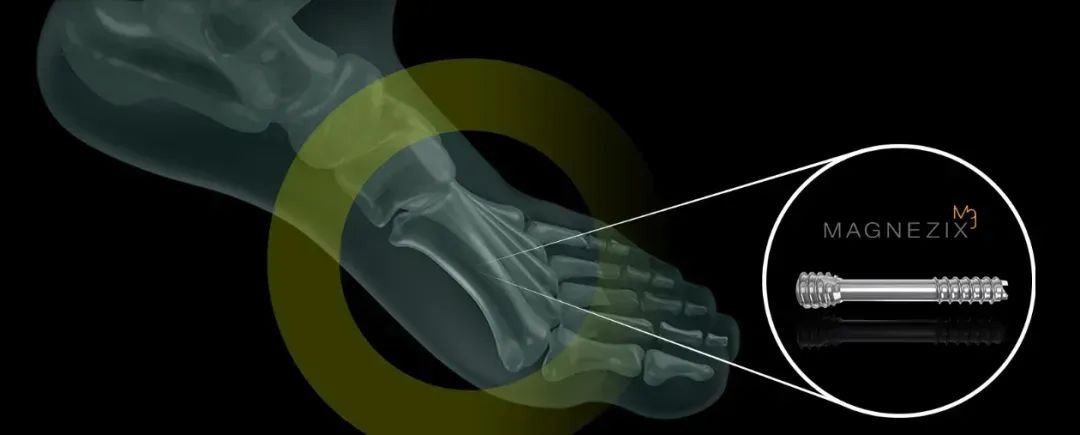

(Syntellix AG)

项目类型

器械质押区

起投金额

2000USDT

每日释放:0.7

释放周期:25 天

已购: 40000

剩余: 0